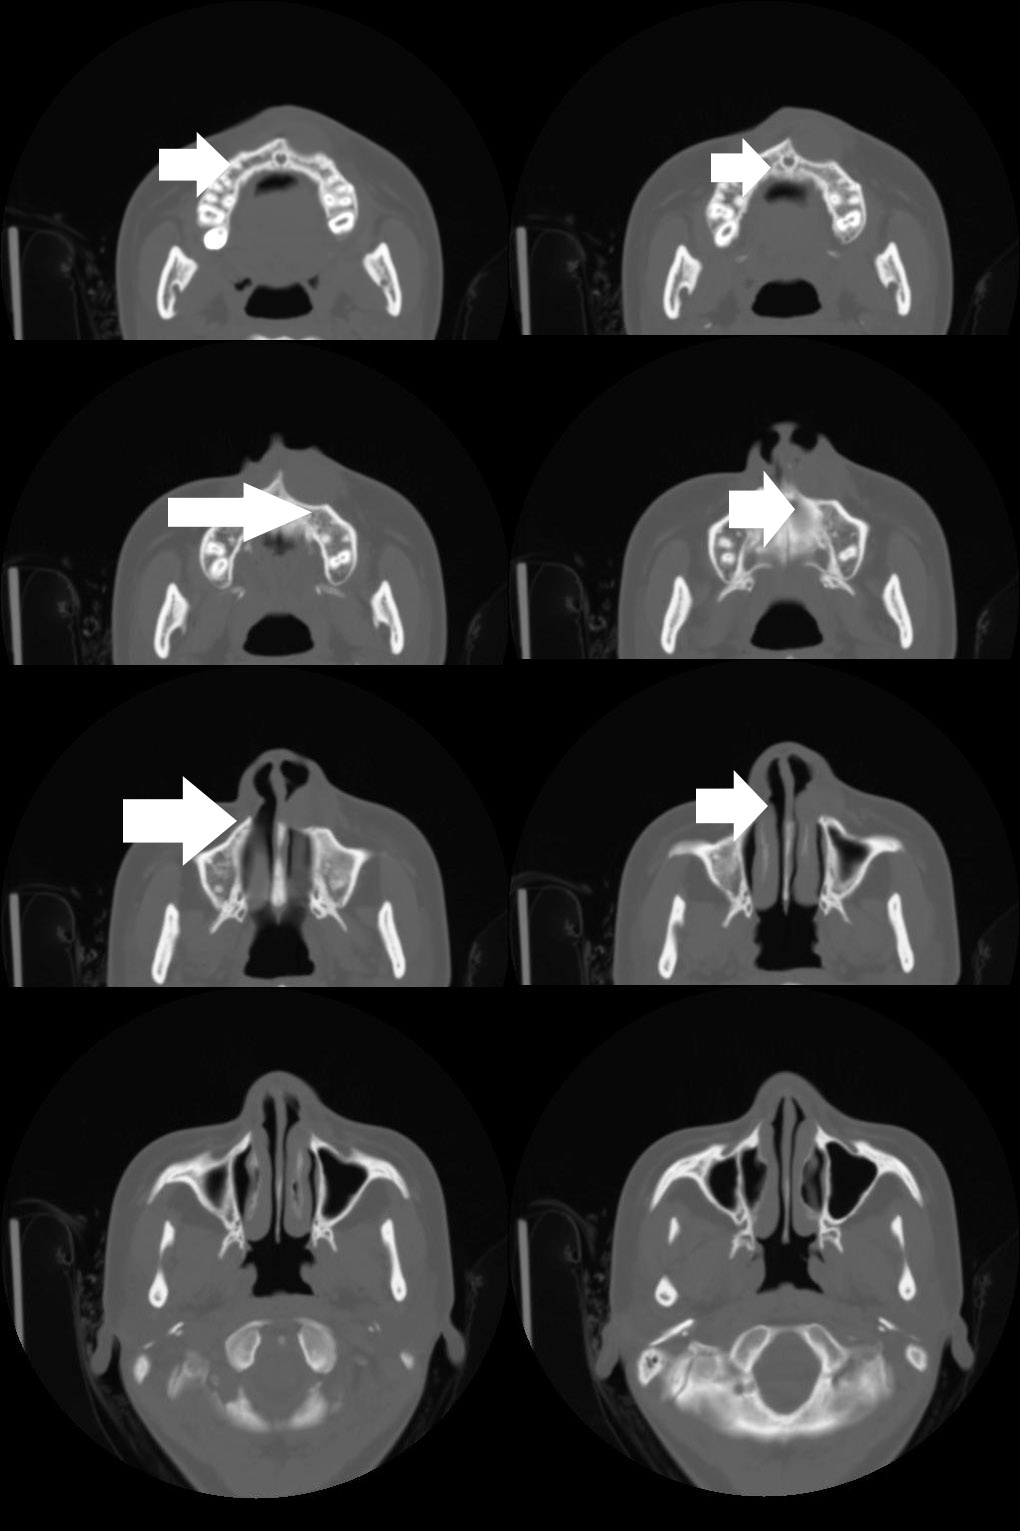

标题: CT7523:[分享]考虑鼻前庭囊肿!

病人诉近20天左鼻侧隆起肿胀